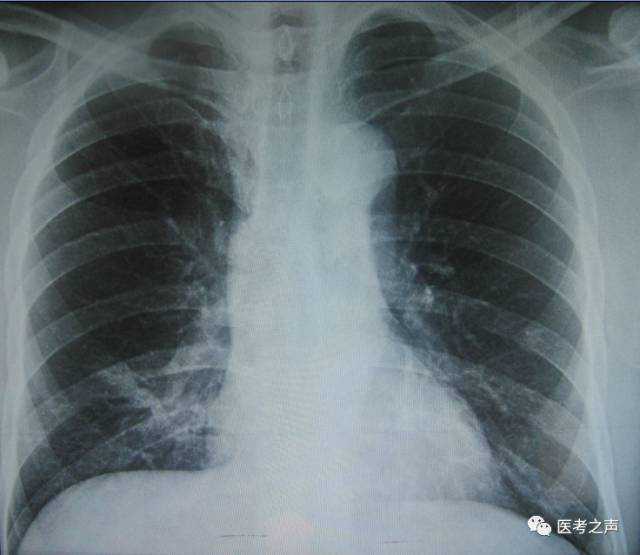

X线

像把面包压扁了看

X光是穿透性很强的射线,能够穿透人体,使用X线对人体内部进行透视或摄影的检查方法,其原理是利用了X线的穿透作用。在穿透人体时,被含钙的成分(骨)、水分(血液等)、软组织(肌肉)等吸收而减弱,X线会穿过人体,遇到被遮挡的部位,底片上不会曝光,洗片后这个部位就是白色的。因此可以呈现出所检查部位的基本形态。

就像一片面包或一块棉花,看不到里面的纤维纹理,但用手压瘪了会清晰一些。X线最大缺点是受制于深浅组织的影像相互重叠和隐藏,有时需要多次多角度拍摄X线片。

3、胸部——粗看X线片,细看CT,看肺不要选核磁

X线胸片可粗略检查心脏、主动脉、肺、胸膜、肋骨等,可以检查有无肺纹理增多、肺部钙化点、主动脉结钙化等。

胸部CT检查显示出的结构更清晰,对胸部病变检出敏感性和显示病变的准确性均优于常规X线胸片,特别是对于早期肺癌确诊有决定性意义。但是CT检查的辐射剂量高于X线。核磁对于肺部疾病的诊断,应用非常有限。